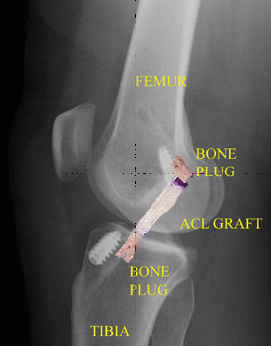

La radiografía posoperatoria después de la reconstrucción del LCA con el tendón rotuliano (con una imagen superpuesta del injerto) muestra la posición del injerto y la fijación de los tapones óseos con tornillos interferenciales metálicos.

En la técnica de reconstrucción del LCA más frecuente, el cirujano perfora túneles en la tibia y el fémur para poder colocar el injerto del LCA con un posicionamiento lo más anatómicamente correcto posible. Una vez colocado el injerto en la rodilla, se mantiene en tensión y se fija en su lugar con tornillos, botones u otro dispositivo. Por lo general, estos dispositivos no se extraen después de la cirugía.